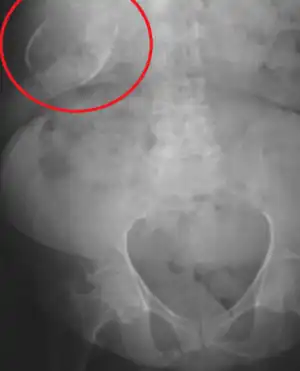

![]() | |

| Porcelain gallbladder on X-ray | |

Abdominal radiography (X-ray), abdominal ultrasound or CT scan.